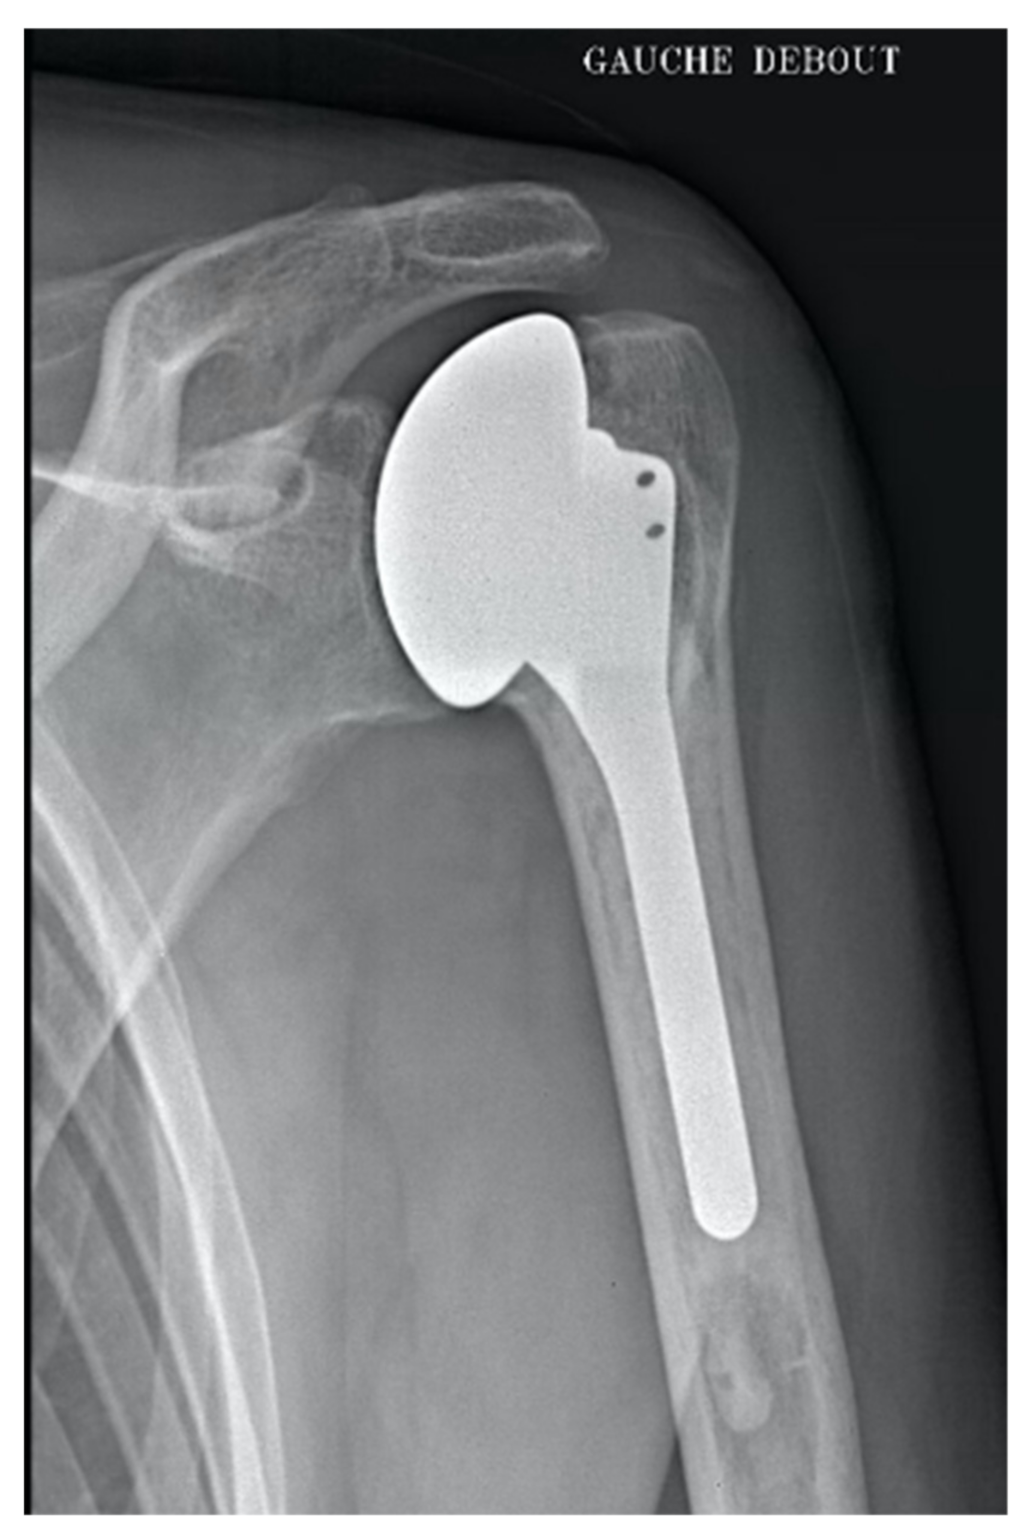

2.4. Total Anatomic Arthroplasty